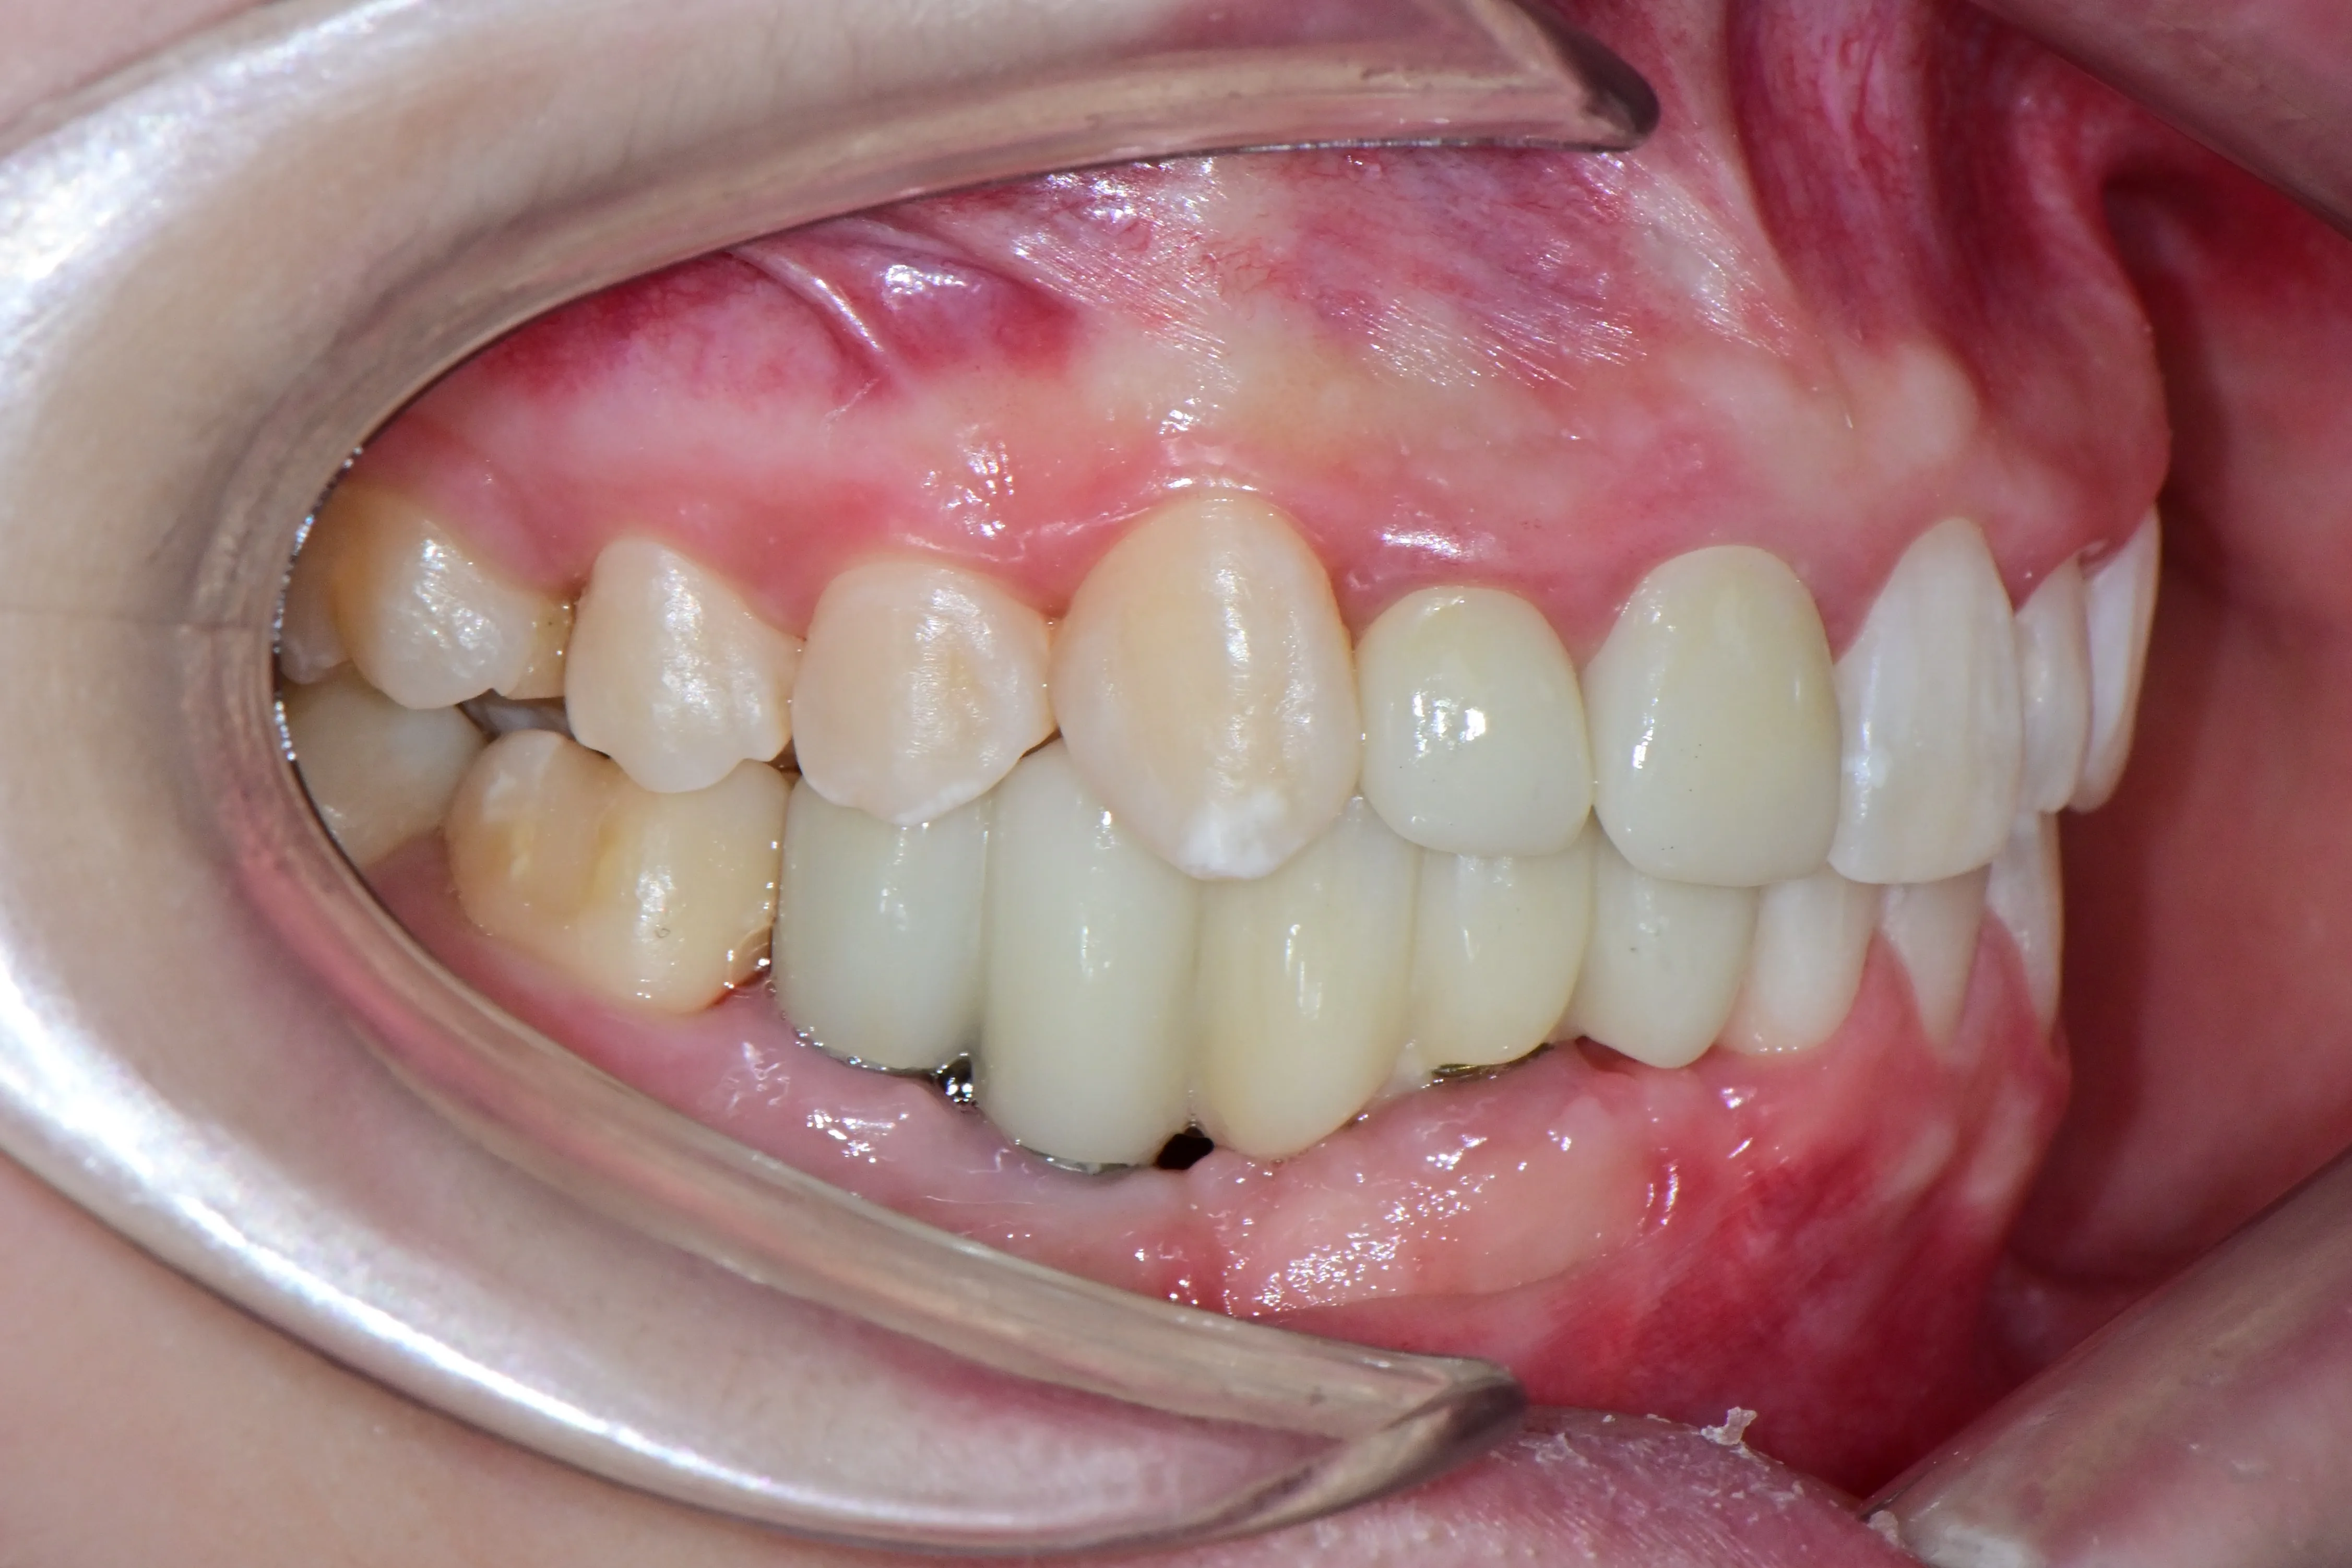

치료후 (After)